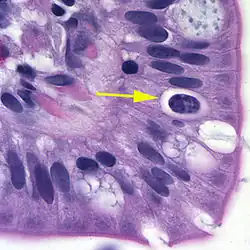

| Oocyst in epithelial cyst of mammalian host | |